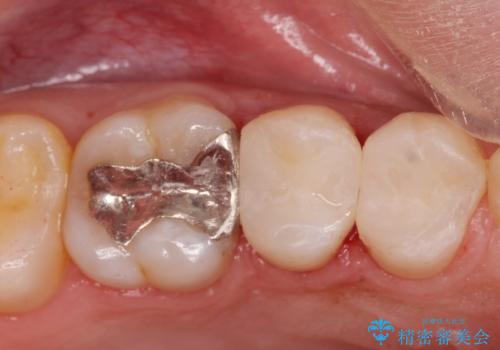

コンタクトカリエス治療。

- 歯と歯の間に虫歯(コンタクトカリエス)が見られたので拡大鏡下で取り除き、e-maxインレーで治療を行いました。

- e-maxインレー 7.7万費用は治療当時の料金となります